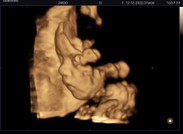

ทีมธันวาโชว์อัลตร้าซาวด์เบบี๋กันค่ะ

บ้านนี้ได้ลูกชาย แม่ๆทีมธันวาได้ลูกสาวหรือลูกชายกันคะ